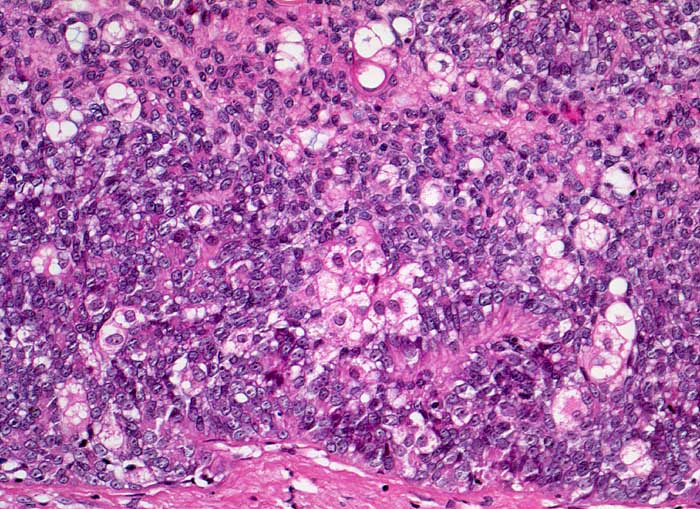

Sebaceom

benigner Tumor

Haut, Rumpf

Haut

Grosser solider Verband aus gering differenzierten, monomorphen basaloiden Zellen mit Einschluss von einzelnen Zellen und kleinen Zellgruppen mit breitem, hellem, grob vakuolisiertem Zytoplasma.

Talgdrüsentumoren sind gehäuft beim Muir-Torre Syndrom. Sebazeome müssen von Talgdrüsenkarzinomen unterschieden werden, die charakterisiert sind durch invasives Wachstum, Zellpleomorphie und Atypie, zahlreiche auch atypische Mitosen und oft Massennekrosen aufweisen.

Histologie

200